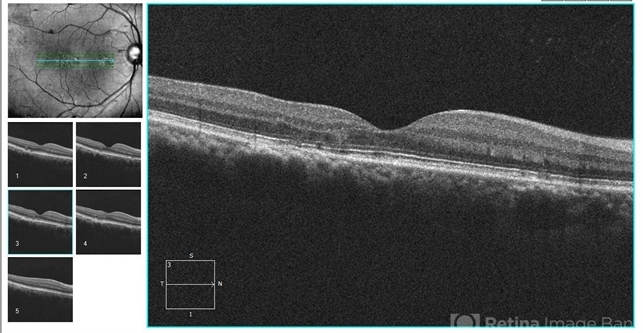

- optical coherence tomography (OCT), retinal pigment epithelium

- Eitae Kim, BOIM retinal center, Pureun eye hospital

Optical coherence tomography system

Cirrus, Zeiss - Description

- OCT image of 51-year-old male with recurrent retinal pigment epithelitis.